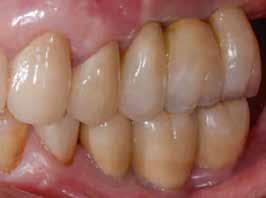

Egy fiatal páciens jelentkezett nálunk, akinek eltörött a szabad véggel rendelkező hídja (1. ábra). A hiányzó, első premoláris fog esetén implantációs pótlást javasoltunk. A csontállomány értékeléséhez CBCT-vizsgálatot végeztünk, és az elemzéséhez NNT Viewert (NewTom) használtunk, és copaSKY 4×10 mm-es (bredent medical) implantátumot választottuk a fog pótlásához

1. ábra: Műtét előtti fogászati panorámafelvétel, amelyen a hiányzó felső állcsont jobb első premolárisát és a szabad véggel rendelkező hidat láthatjuk. — 2. ábra: Az implantátum méreteinek megtervezése CBCT-vel. 3. ábra: Bukkális lágyrészdefektus. — 4. ábra: A biológiai szélesség értékelése a vertikális lágyszövetvastagság alapján. 5. ábra: Palatinális „tekercslebeny” – Palatal roll flap. — 6. ábra: Bredent medical copaSKY 4x10 implantátumbeültetés. 7. ábra: Szubkresztális implantátumbeültetés a várható biológiai szélességnek megfelelően.

(2. ábra). A lágyszövetek értékelése Seibert szerinti I. osztályú csontdefektust állapított meg (3. ábra), ezért a beavatkozáskor palatinális „tekercslebenyt” preparáltunk (palatal roll flap), és implantációt végeztünk, hogy kompenzálni tudjuk a bukkális lágyszövet-behúzódást. Megmértük a vertikális lágyszövetvastagságot, és úgy terveztük, hogy a szubkresztális implantátum beültetése összhangban legyen a biológiai szélesség kialakulásával a transzgingivális gyógyulási periódus alatt (4. ábra)